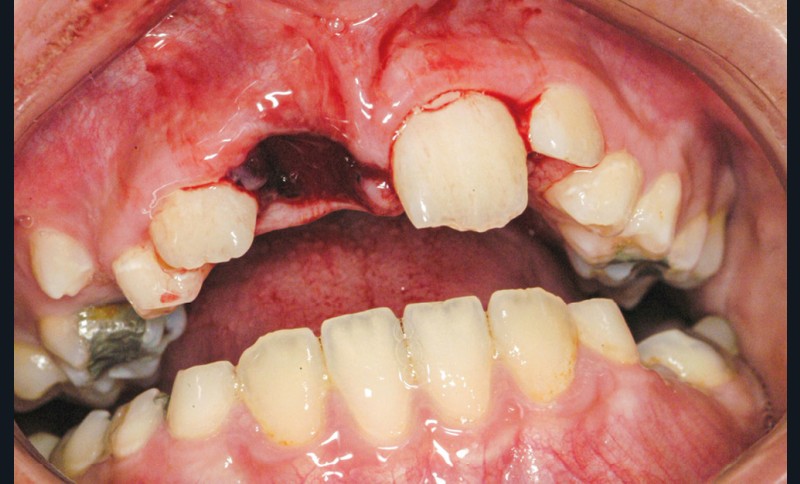

Enfant de 9 ans dont une incisive centrale maxillaire a été expulsée en jouant au football. Appel immédiat de la mère à qui l’on conseille de conserver la dent expulsée dans du sérum physiologique (fig. 1). Le temps extra-alvéolaire à sec a été inférieur à 5 minutes. Le patient arrive 40 minutes après le traumatisme dans l’Unité d’Odontologie pédiatrique. Après interrogatoire, examen clinique et radiographique, un rinçage de l’alvéole est effectué et la dent est réimplantée le plus rapidement possible (fig. 2). Une contention semi-rigide est ensuite placée (fig. 2). La dent étant mature, la prise en charge endodontique (séance de Ca(OH)2 puis obturation à la gutta percha) débute deux semaines plus tard (fig. 3 et 4) afin de limiter les risques d’infection, de résorption. Le suivi sur quatre années montre une dent fonctionnelle, sans ankylose ni résorption radiculaire ou osseuse.